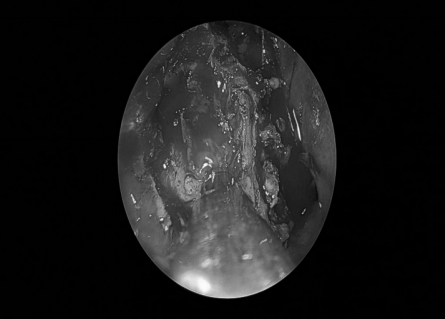

耳内镜检查:分泌性中耳炎(右)

双耳鼓膜完整,右侧鼓膜内陷明显,右侧鼓室可见积液